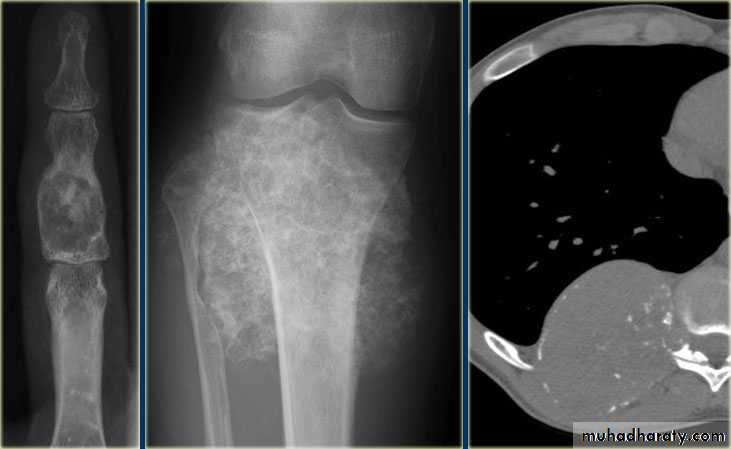

the initial radiological decision is usually to try &decide whether the solitary lesion is benign or its aggressive by looking for the following features on plain radiographs & CT :

1.Zone of transition

2.The adjacent cortex

3.Expansion

4.Periosteal reaction

5. Calcific densities within the lesion

6. Soft tissue swelling

7.Site:The site of a lesion is most important as certain lesions tend to occur at certain sites.Bone tumours

Primary malignant tumoursOsteosarcoma ( osteogenic sarcoma )

Chondrosarcoma :

Ewing sarcoma

Giant cell tumour